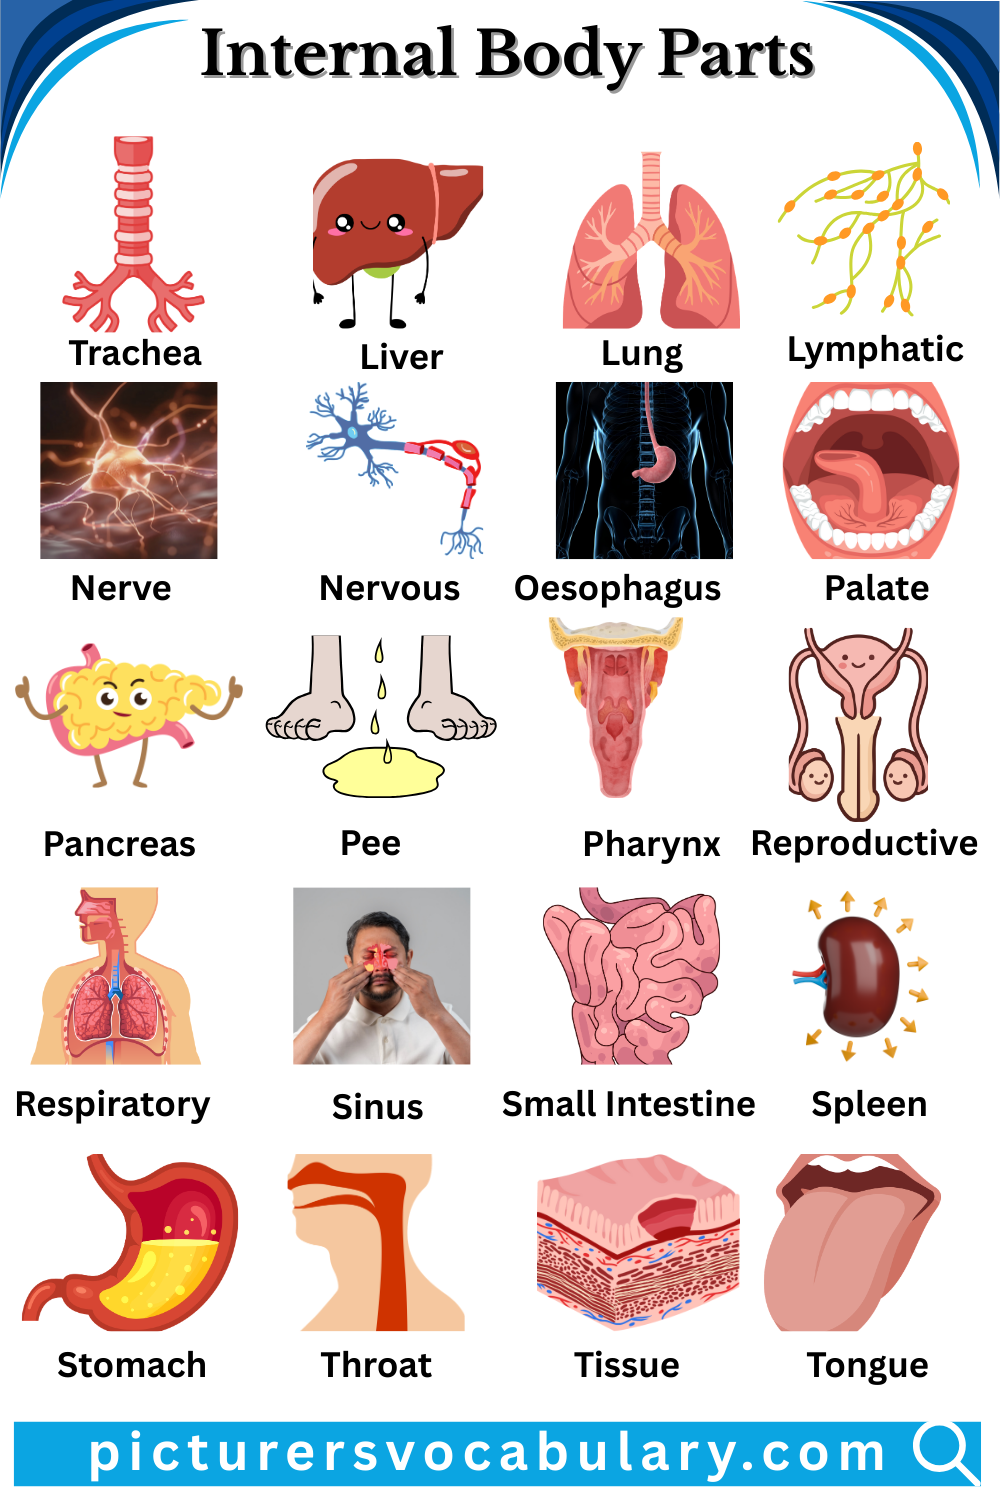

Internal Body Parts Vocabulary With Pictures

List of internal body parts is given below:-

Liver

The liver is a glandular reddish-brown organ that produces bile and helps in metabolism and detoxification.

Lung

The lung is a saclike respiratory organ in the chest that exchanges oxygen and carbon dioxide.

Lymphatic

The lymphatic system contains clear fluid and white blood cells.

Nerve

A nerve is a bundle of fibers connecting organs and tissues.

Nervous

The nervous system controls sensory functions.

Oesophagus

The oesophagus is a passage from the pharynx to the stomach.

Palate

The palate forms the roof of the mouth between the oral and nasal cavities.

Pancreas

The pancreas is a large gland that produces insulin and digestive enzymes.

Pee

Pee means to eliminate urine.

Pharynx

The pharynx is a passage that leads to the stomach and lungs.

Reproductive

The reproductive system is used for producing offspring.

Respiratory

Respiratory relates to breathing.

Sinus

A sinus is an abnormal passage or cavity near a surface.

Small Intestine

The small intestine is the longest part of the alimentary canal.

Spleen

The spleen is a large oval organ near the stomach and diaphragm.

Stomach

The stomach is a muscular saclike part of the alimentary canal.

Throat

The throat is a passage that leads to the stomach and lungs.

Tissue

Tissue is an aggregate of cells.

Tongue

The tongue is a mobile muscular tissue in the oral cavity.

Trachea

The trachea is a tube that connects the larynx to the lungs.